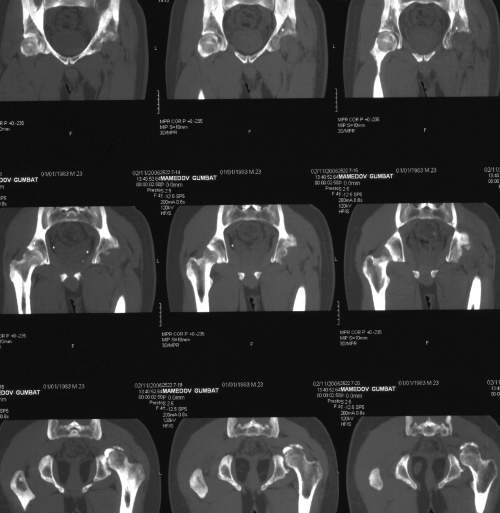

важаемые коллеги,пациент 23 лет (вес 75 кг), обратился к нам по поводу боли в тазобедренном суставе при ходьбе, нестабильность в нем при нагрузке. Ходит с тростью. 8 мес. назад попал в ДТП (никаких медицинских документов у него нет). Стоит ли открываться и вправлять вывих или сразу делать бесцементное тотальное эндопротезирование? С уважением, А. В. Вакуленко Клиника эндопротезирования суставов, г. ДонецкDear All, male patient 23 y.o., body weight 75 kg. Had RTA 8 months ago (medical records unavailable). Now has pain on motion in his left hip. On weight-bearing hip is unstable (patient use cane while walking). Keeping in mind his age, is it worth to perform open reduction? Or just do uncemented THR? Any comments are very welcome.

After 8 months, the hip will not easily come down into the acetabulum. It also appears to me that there is an impression fracture of the head of femur.

Здравствуйте. Позвольте поучаствовать в обсуждении. Поскольку пациент в течение 8 месяцев не получил адекватного лечения (видимо и по своей вине тоже), а также учитывая удовлетворительное состояние головки бедра(по данным КТ), есть смысл выполнить открытое вправление головки бедра с возможной фиксацией фрагмента заднего края пластиной. Далее начать восстановление функции сустава, дозированную нагрузку. Возможно молодой возраст пациента поможет ему отдалить время эндопротезирования. Желаю успехов.